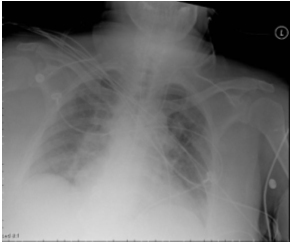

82M BMI 53, SOB, WBC 7.6, Afebrile, ?CHF

Air bronchogram

Evidence: http://www.ncbi.nlm.nih.gov/pubmed/28244009/

Day 4 Not Improving, Spiking Fevers

Complex Pleural Effusion